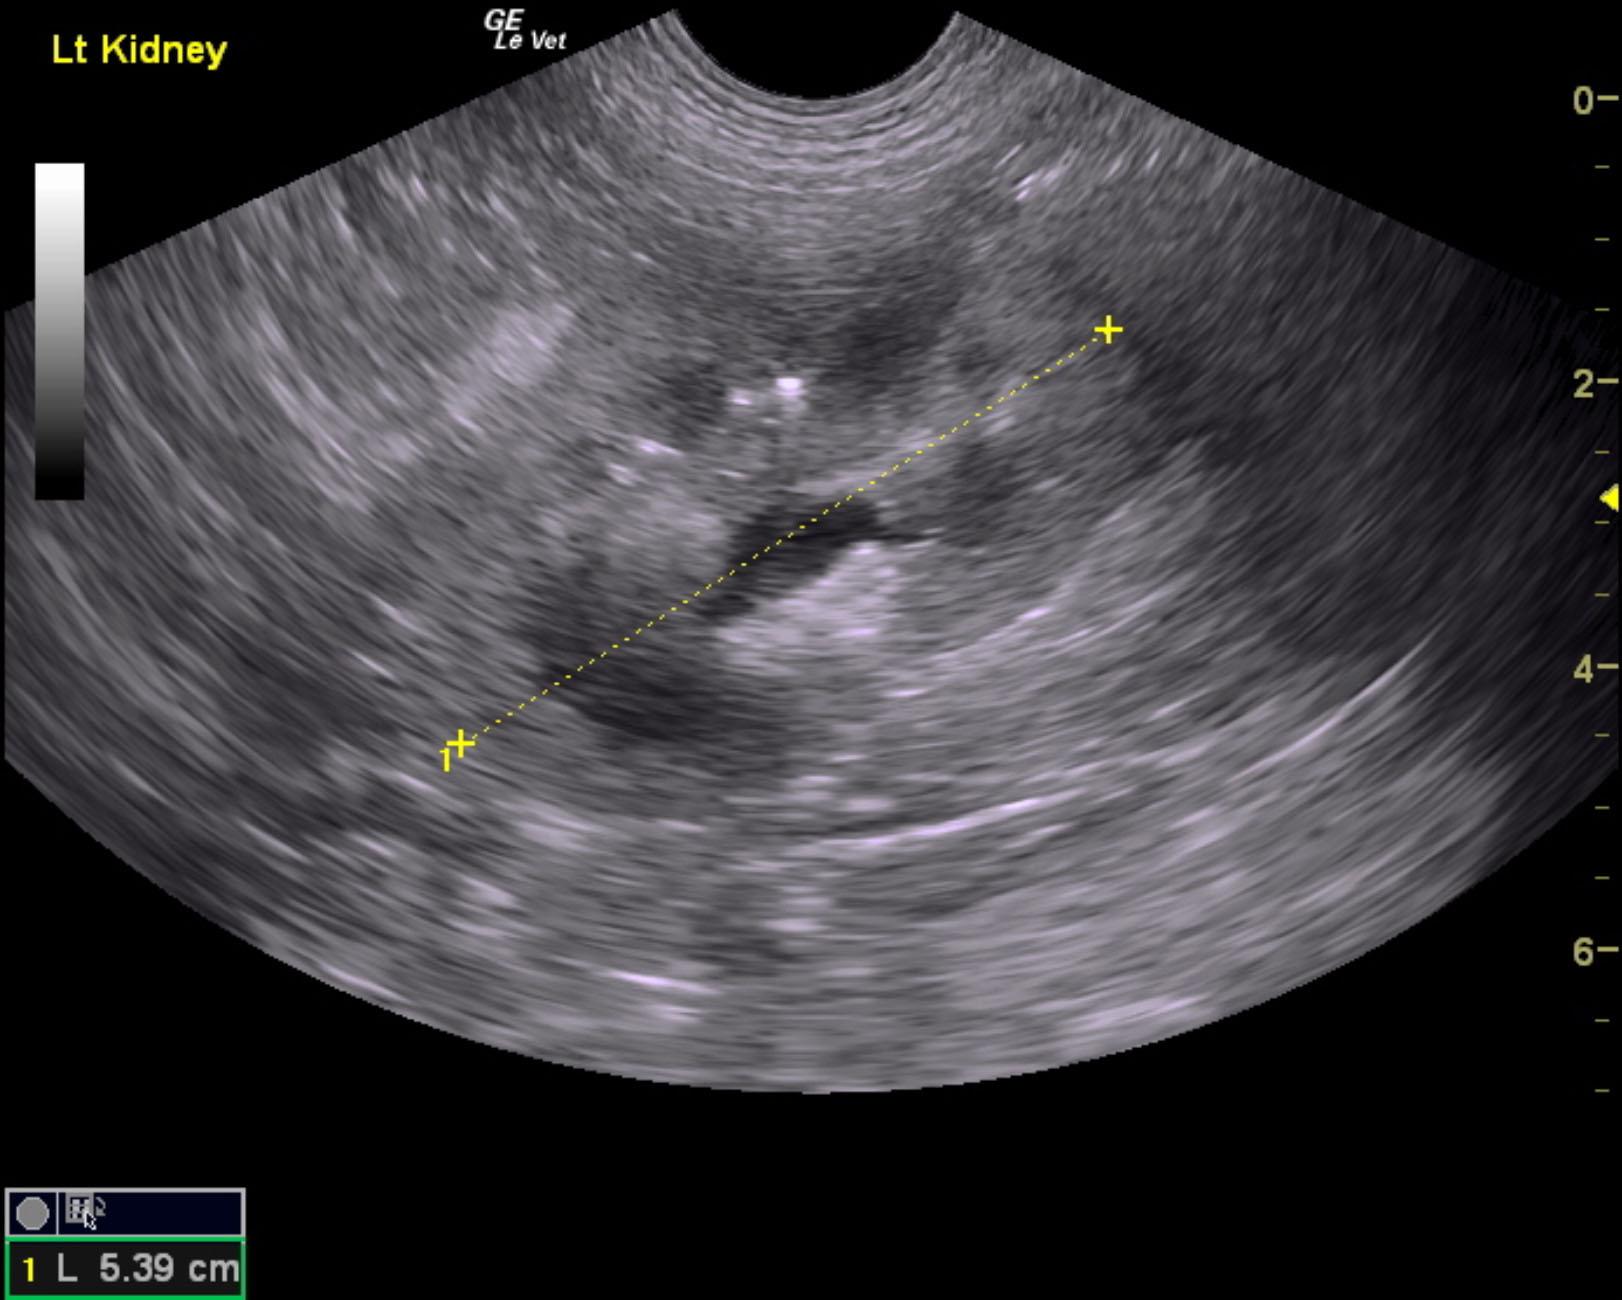

A 5-years-old male neutered Shih Tzu was presented for evaluation of urethral obstruction that had been managed with catheterization. Urinalysis showed SG of 1.008 and proteinuria. Abnormalities on CBC and serum biochemistry were neutrophilia and monocytosis, elevated phosphorus, and azotemia; the latter had improved after being catheterized.